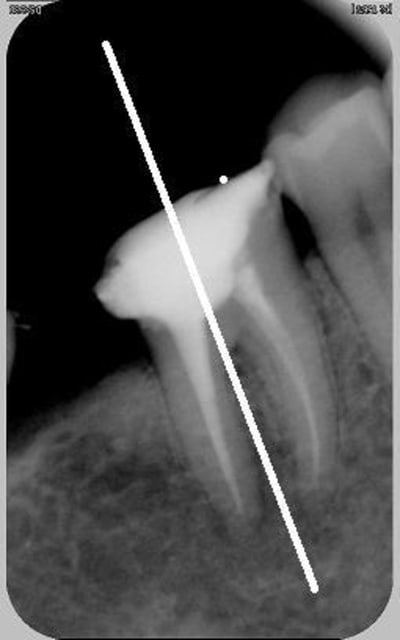

je crois...cet axe là?

Je pense, amigo athos!!! (histoire de trouver qquchose :-))))

Quand je parlais de grand axe de la radio, c'est la longueur du capteur qu'il fallait comprendre, pas celui de la dent radiographiée. En gros, pour des molaires/prémolaires, ta radio doit être regardée comme un écran 16/9. Pour les I et C, comme le portarit de la Joconde.

capteur "couché" alors?

dis donc t'es sur que ça va diminuer les déformations ça? enfin bon, je ferai comme ça desormais, mais si je ne vois pas une amélioration merveilleuse de l'image je serai tout déçu déçu déçu...